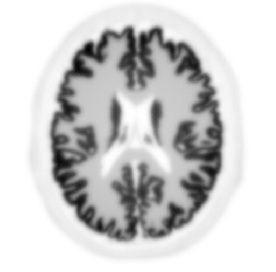

The localization of the emission point of an annihilation pair along a LOR depends on the detection of the time difference between the two annihilation photons, also known as the time-of-flight (TOF) difference of the photons, whose accuracy is given by the coincidence time resolution (CTR). This additional information makes the tomographic inversion problem much less ill-posed, hence resulting, hence resulting in a better signal-to-noise ratio of the activity measurement. Taking into account the speed of light, which is approximately 30 cm/ns, a CTR better than 10 picoseconds FWHM will ultimately allow to obtain a direct 3D volume representation of the estimated activity distribution of a positron emitting radiopharmaceutical, at the mm level and without the need for tomographic inversion, thus introducing a quantum leap in PET imaging and quantification.

Non-TOF back-projection

TOF back-projection with 10ps FWHM CTR

Hoffman brain phantom simulated analytically without noise (courtesy: Johan Nuyts, University of Leuven).